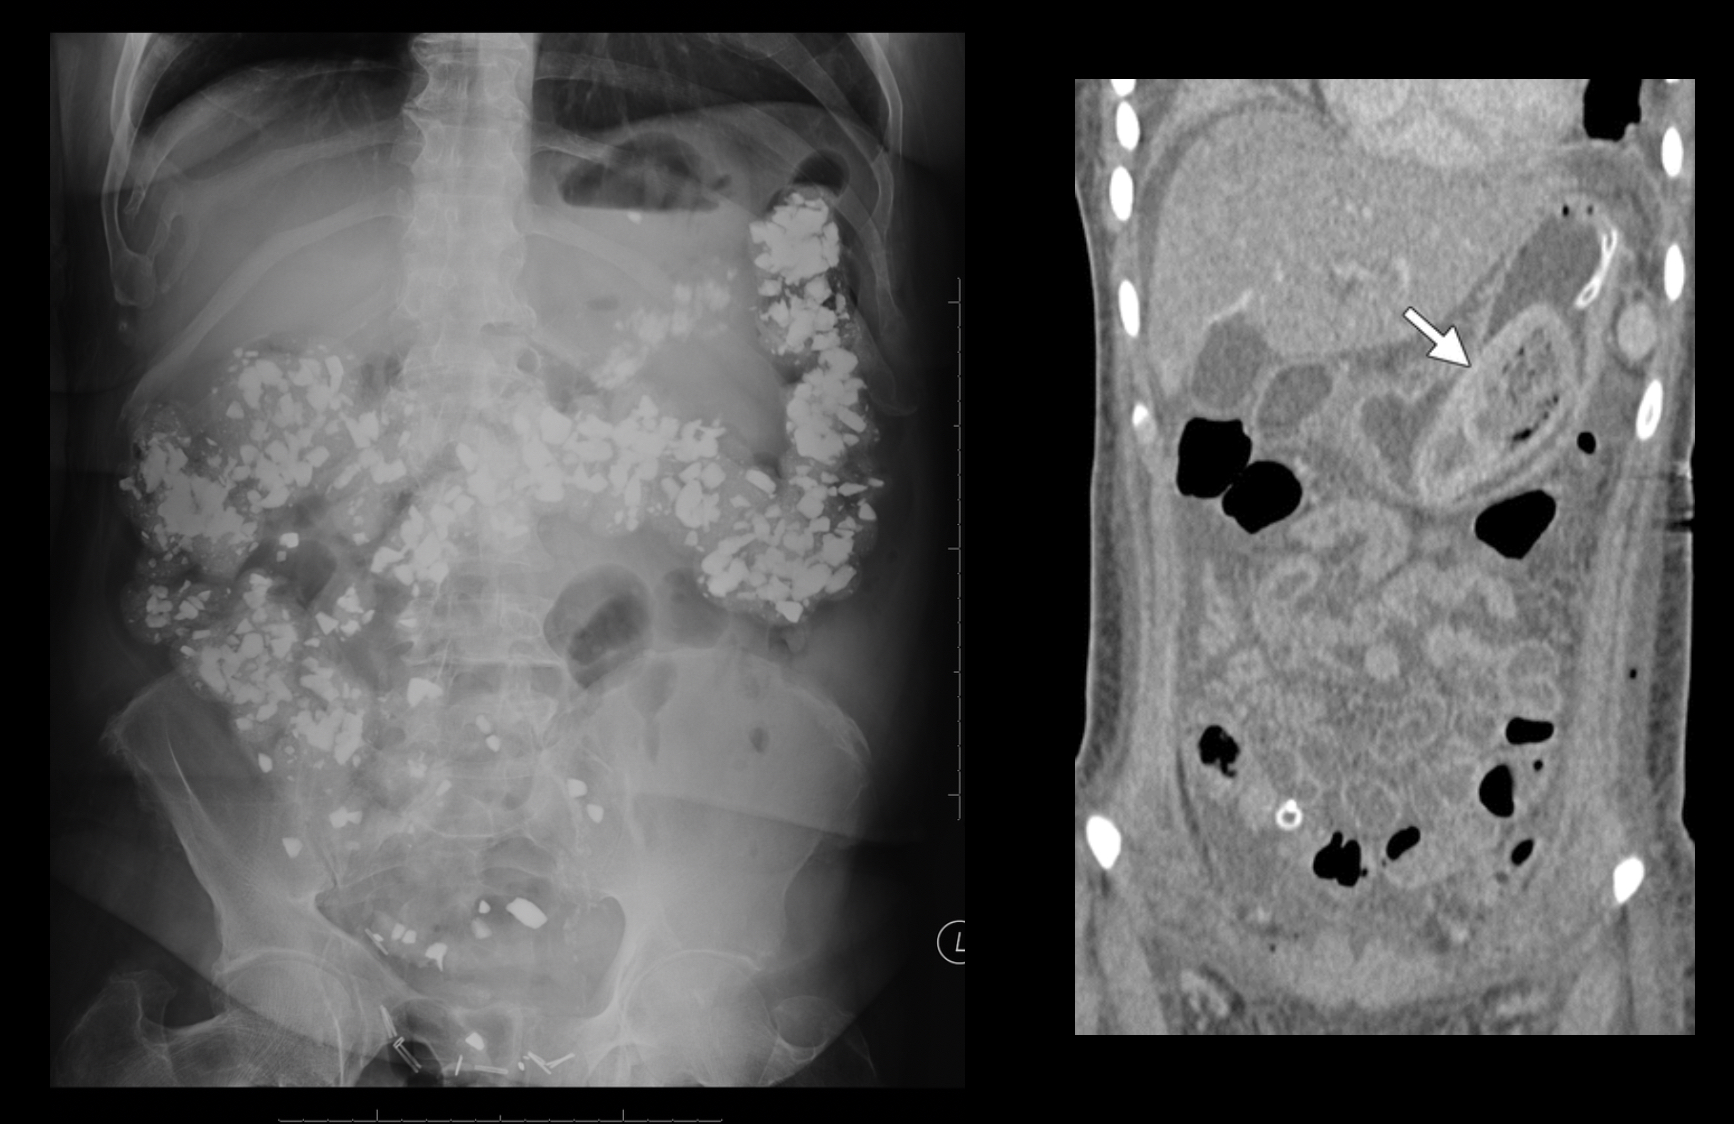

pica

psychological disorder of intentional and craving consumption of non-nutritive substances over a period of time

radiographic appearance of pica

appearance of foreign objects/ substances

technical factors of pica

depending on blockage, may need to increase

What pathology is this?